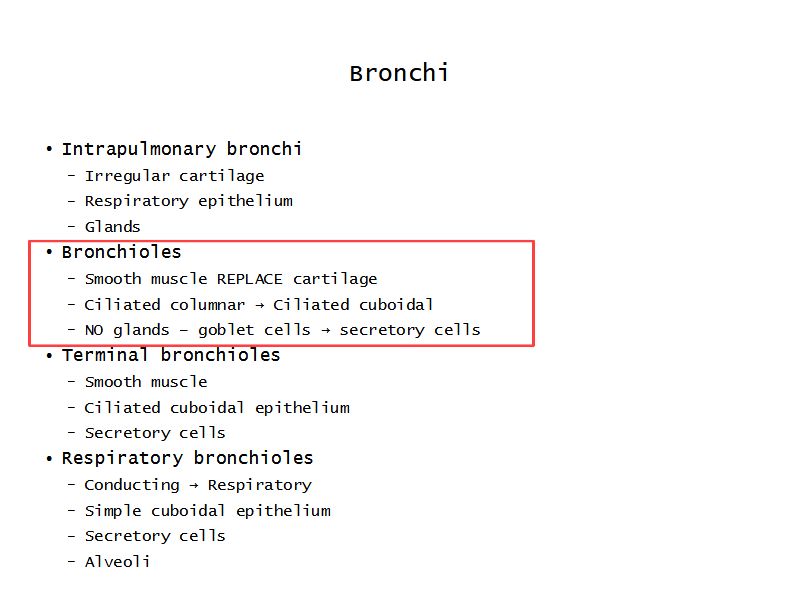

Respiratory epithelium

- Pseudostratified

- Ciliated

- Columnar

- Epithelium with

- 4 Cells

- Ciliated columnar cells

- Non-ciliated columnar cells

- Goblet cells

- Basal cells